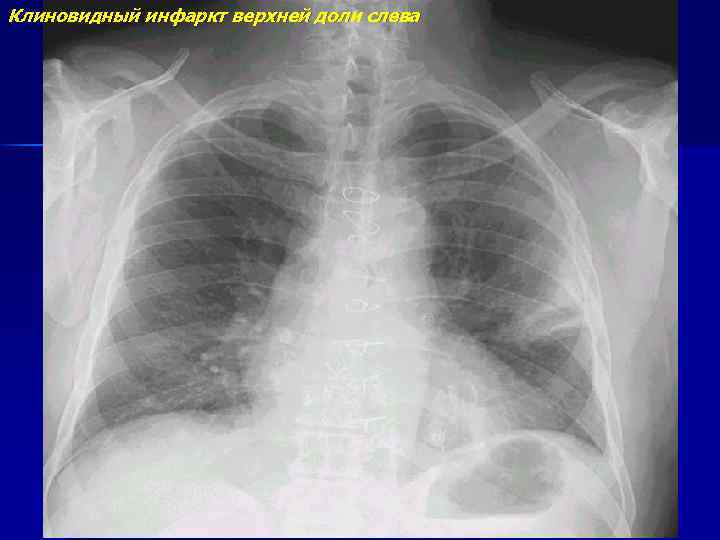

Клиновидный инфаркт верхней доли слева